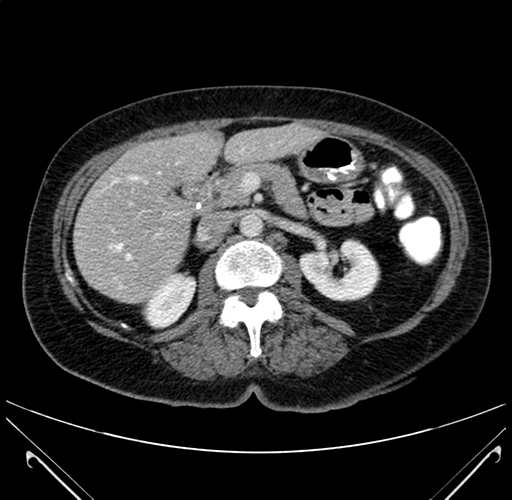

Axial Venous